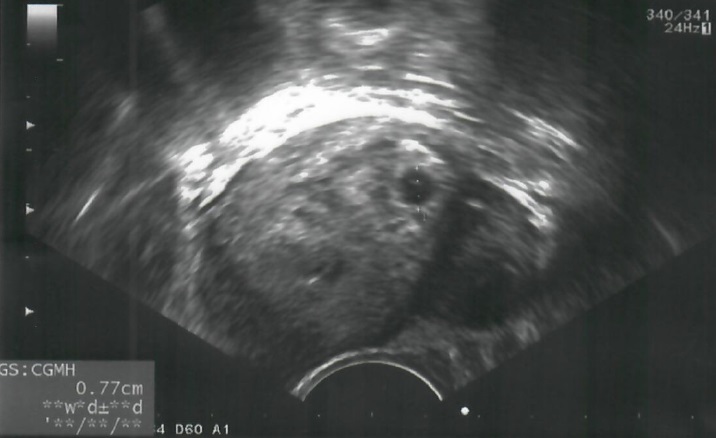

林小姐回想,當試管補助方案正式在7/1上路之後的隔天,回到醫院門診,林醫師通知了這個好消息,他們也立即在院內完成申辦手術,並和醫師討論是否在7月進行植入。林秉瑤醫師說明:「如果病人的狀況單純,沒有其他複雜的問題,採取單顆正常胚胎的植入成功率就能高達7成以上;加上,為了保障她孕期和產程的安全性,最佳的治療方案應以單胞胎活產為主。」於是,夫妻倆接受林醫師的建議,並在7月上旬順利完成植入。